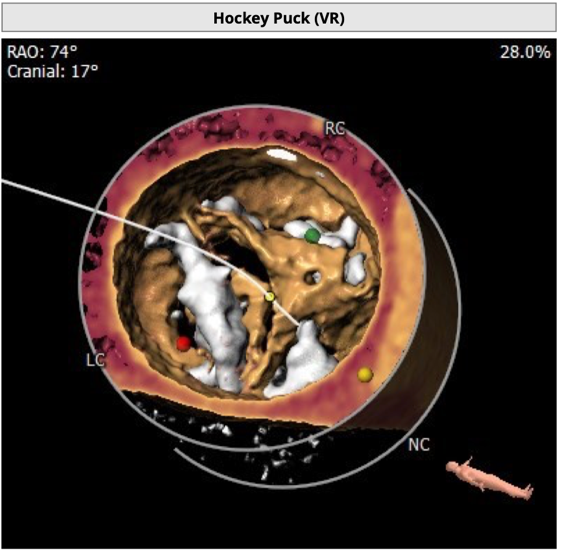

CT 数据显示该患者为Type1型二叶式主动脉瓣

瓣叶严重粘连增厚,瓣叶钙化明显,HU850:1448.3mm³。

左冠开口高度8.6mm,右冠开口高度15.0mm,左冠高度偏低,左冠瓣瓣尖钙化明显,根据瓦氏窦内径和瓣叶长度综合判断,左冠存在较高堵塞风险;左心室后壁增厚。

1 患者为Type1型二叶式主动脉瓣,右无融合并形成钙化嵴,瓣叶极重度钙化伴严重增厚粘连;

2 患者左冠开口偏低,左冠瓣瓣尖钙化,结合瓦氏窦内结构,存在较大左冠堵塞危险;